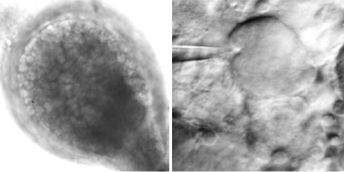

A major new insight into how Hepatitis B Virus works could pave the way for new drug treatments for the infection which is the major cause of liver cancer worldwide.